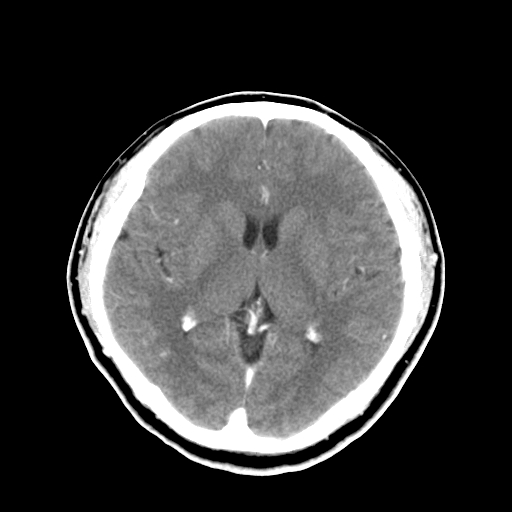

标题: CT16447B:(续)增强扫描图像。

患者今日做ct增强检查,现补传增强扫描图像。

松果体钙癍增大,无其他改变,定不了性

一般认为大于1cm为异常。